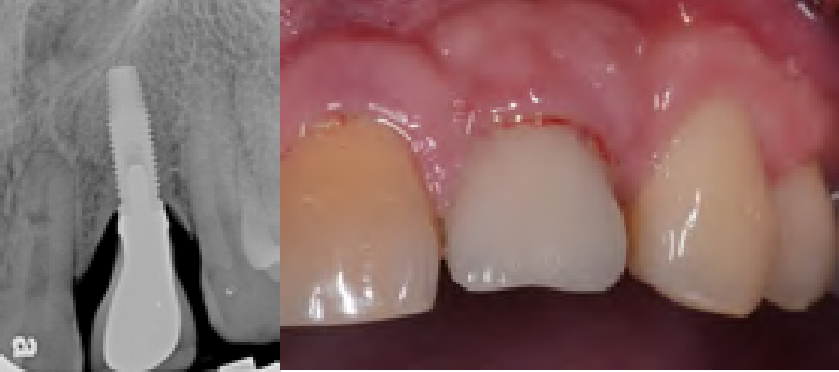

Fig 11. Pretreatment radiograph (left) of an implant placed 14 years earlier that developed peri-implant mucositis—with bone loss from the cuspid, and the initial soft-tissue perspective (right) showing puss and bleeding. Initial probing depths were 7 mm to 8 mm.

Figure 11

Fig 14. At 3 months after laser treatment, there was absence of bleeding on probing, and shallow probing depths of only 3 mm compared to pre-treatment.

Figure 14